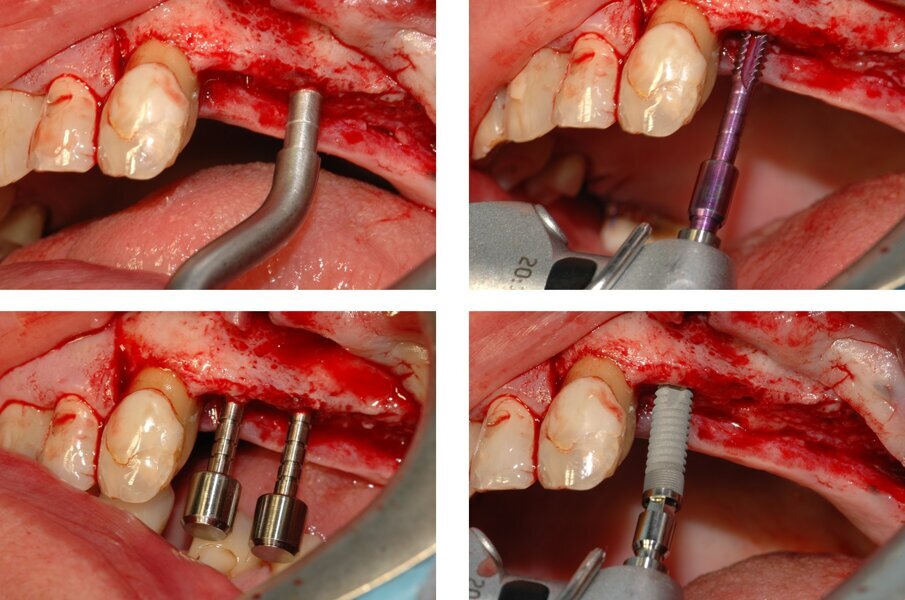

L’area di intervento è stata anestetizzata utilizzando articaina cloridrato 40 mg con adrenalina 1:100000. Si è proceduto quindi a sollevare un lembo a tutto spessore, leggermente paracrestale, e a raccogliere del particolato autologo, utilizzando un bone scraper (SafeScraper Twist, Meta, Reggio Emilia) da impiegare successivamente per l’innesto miscelandolo col biomateriale (Fig. 2).

Si è proceduto quindi all’inserimento del primo impianto (Stone, IDI Evolution, Concorezzo) in posizione 2.5, previa misurazione della densità ossea attraverso una sonda di misura, connessa al manipolo di un apposito micromotore (TMM2, IDI Evolution, Concorezzo) e alla preparazione del sito per l’inserimento dell’impianto in posizione 2.6 (Fig. 3). L’osteotomia è stata eseguita utilizzando inserti piezoelettrici; la membrana sinusale è stata quindi scollata e sollevata e si è proceduto alla preparazione del sito implantare destinato ad accogliere il terzo impianto in posizione 2.7 (Fig. 4). La preparazione dei siti in posizione 2.6 e 2.7 è stata anch’essa eseguita previa lettura della densità ossea; essendo la stessa ridotta, si è deciso – per tutti e tre gli impianti – di impiegare un protocollo di sottopreparazione ove l’ultima fresa aveva un diametro inferiore a quello della spira dell’impianto del 12.5% come descritto anche in Arosio et al.14.

Fig. 2_Aperto un lembo a tutto spessore si è proceduto a raccogliere del particolato autologo da miscelare con un sostituto osseo granulare.

Fig. 3_La preparazione dei siti implantari in posizione 2.5 e 2.6 ed il posizionamento del primo impianto in posizione 2.5. Prima dell’allargamento del sito implantare utilizzando l’ultima fresa, la densità ossea viene letta attraverso una sonda collegata al manipolo di un apposito micromotore (seconda immagine in alto); l’informazione è utilizzata per decidere razionalmente un opportuno protocollo di sottopreparazione.

Fig.4_Esecuzione dell’antrostomia, sollevamento della membrana sinusale e preparazione del terzo sito implantare in posizione 2.7. Anche in questo caso, la preparazione del sito implantare è preceduta dalla misura quantitativa della densità ossea (non mostrato).